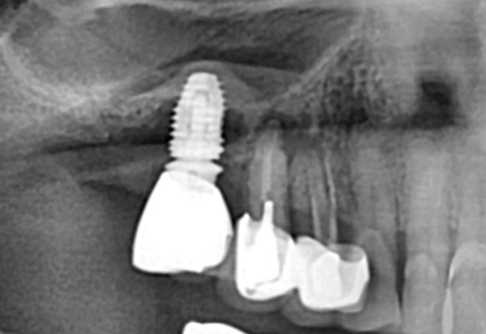

Before

After

위 치료 사례는 굿프렌즈치과에서 직접 치료를 받은 환자 분의 사례로 직접 동의를 얻어 게재되었습니다.